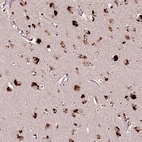

Immunohistochemical staining of human cerebral cortex shows strong cytoplasmic positivity in neuronal cells.